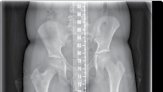

| Operative planning | |||

| Recent radiographs must be available. These should include full leg length views, in the anteroposterior plane, of both lower limbs with the patellae facing forwards and appropriate lateral views. The mechanical and anatomical axes need to be assessed on both legs. If both legs are ‘abnormal’, standard angles are used for calculations. | |||

| Leg length discrepancy | |||

| Assessment is made from history, examination and radiological findings. Care must be taken to differentiate true from apparent causes of leg length discrepancy. | |||

| Preoperative planning See ‘Principles of limb reconstruction’ (p. 427) (Figure 15.8). Surgical technique Corticotomy Landmarks | |||